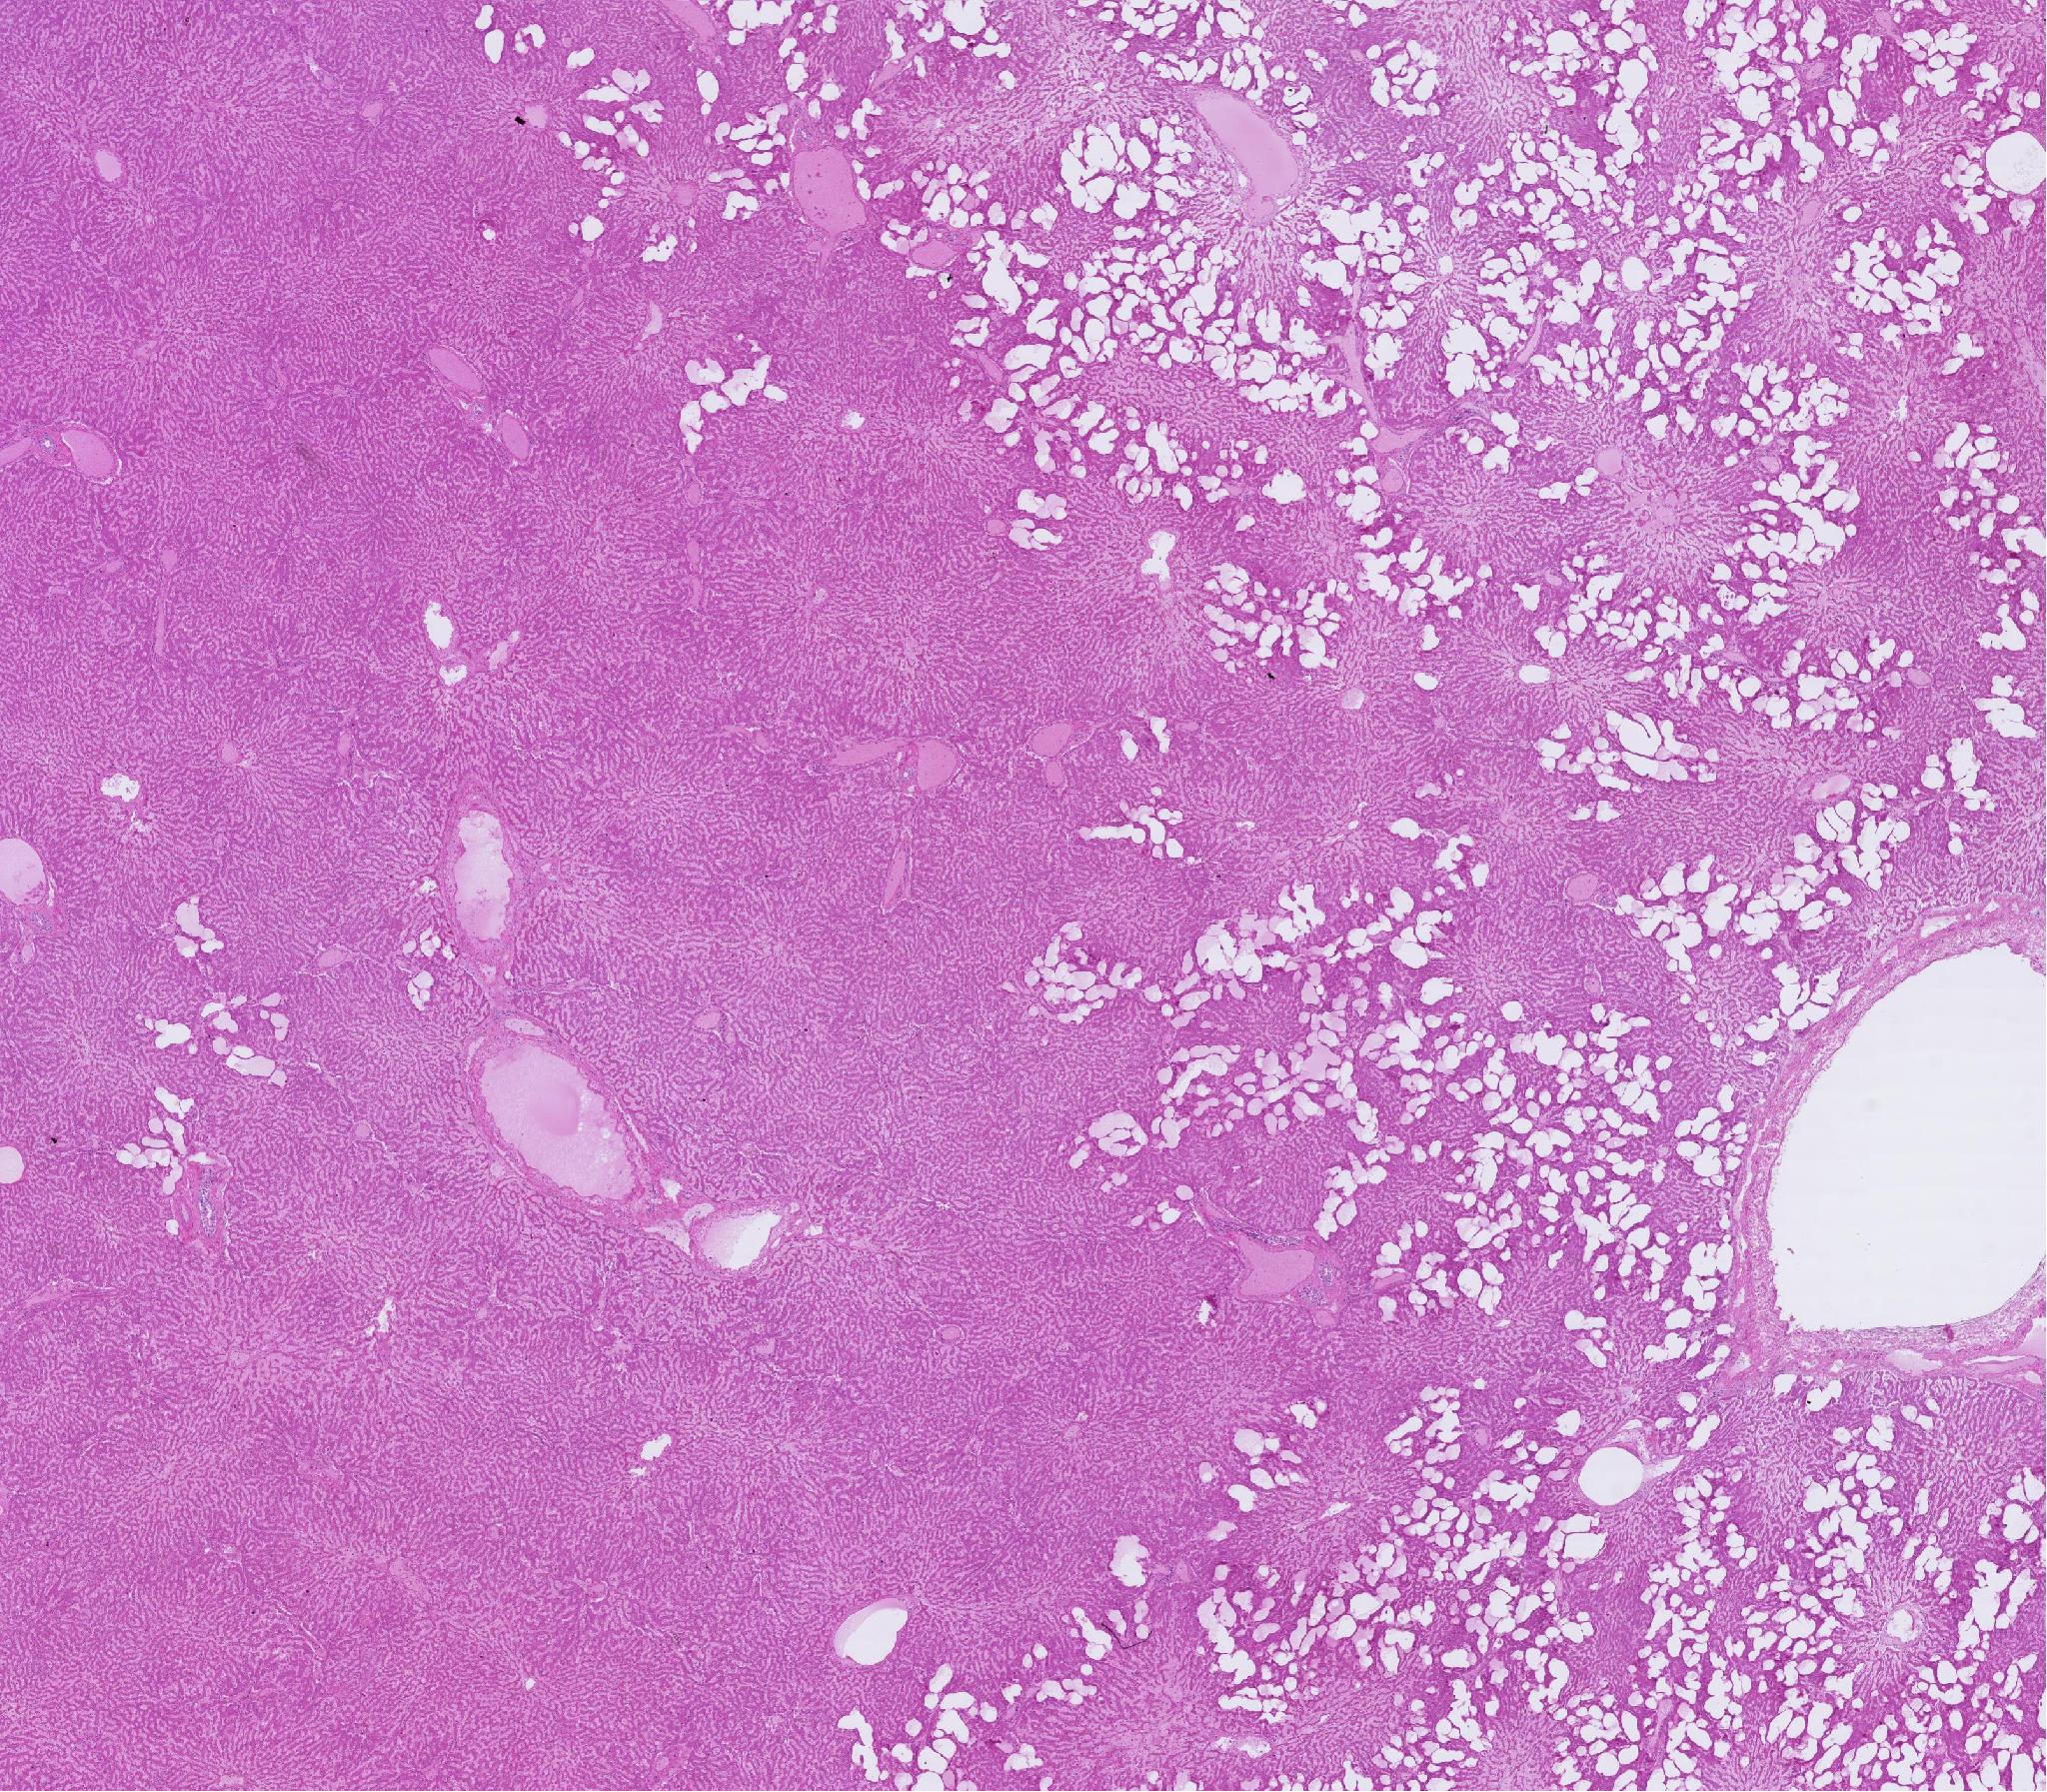

Pathology, 09006-5, lung

호흡기 / /

09006-5